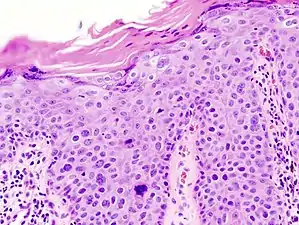

Histopathologically, the epidermis in SCC in situ (Bowen’s disease) will show hyperkeratosis and parakeratosis. There will also be marked acanthosis with elongation and thickening of the rete ridges. These changes will overly keratinocytic cells which are often highly atypical and may in fact have a more unusual appearance than invasive SCC. The atypia spans the full thickness of the epidermis, with the keratinocytes demonstrating intense mitotic activity, pleomorphism, and greatly enlarged nuclei. They will also show a loss of maturity and polarity, giving the epidermis a disordered or “windblown” appearance.

Two types of multinucleated cells may be seen: the first will present as a multinucleated giant cell, and the second will appear as a dyskeratotic cell engulfed in the cytoplasm of a keratinocyte. Occasionally, cells of the upper epidermis will undergo vacuolization, demonstrating an abundant and strongly eosinophilic cytoplasm. There may be a mild to moderate lymphohistiocytic infiltrate detected in the upper dermis.[33]

Histopathology of squamous cell carcinoma in situ (black arrow), compared to normal skin, showing marked atypia.

Squamous cell carcinoma in situ, showing prominent dyskeratosis and aberrant mitoses at all levels of the epidermis, along with marked parakeratosis.[33]